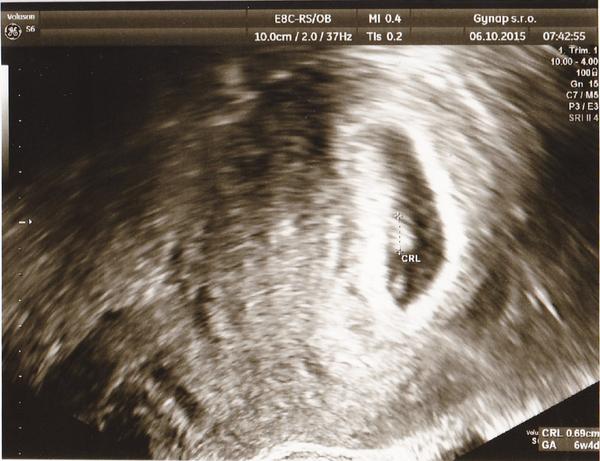

@tynulkaxix ahooj takze je vsetkoo ok som rada ☺☺aj ti byva zle?nejake priznaky??? Prikladam moju foto z ultrazvuku 5tt+4 a mame 8mm

Ahojky holky tak už jsem po kontrole. Miminko krasne roste, mám 6,1 mm, srdíčko bije jako zvon takjsem dostala tehu průkazku🙂 podle poslední ms Máme byt 7+0 ale ddíky mim nepravidelnými cyklu které byly většinou 32 tak jsme 6+3 takže to krasne vychází 🙂